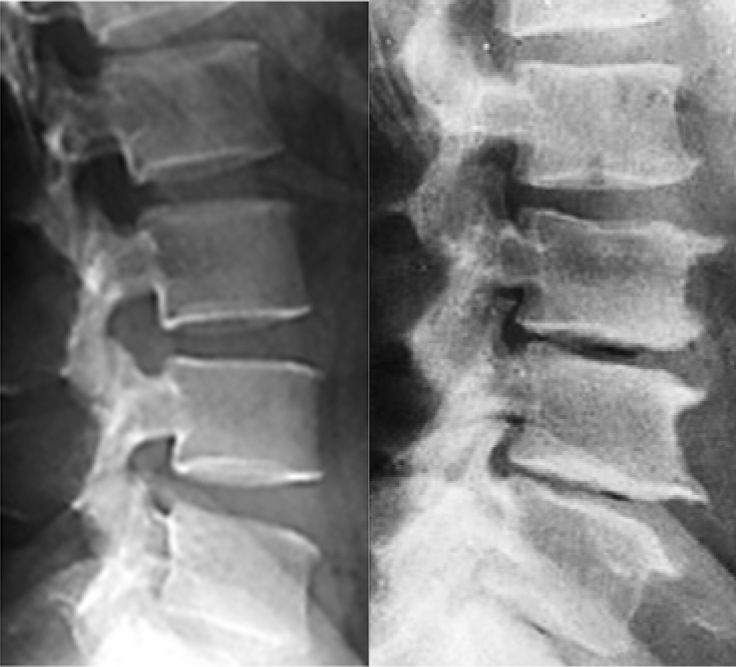

สามารถวินิจฉัยได้จากการซักถามประวัติและตรวจร่างกายโดยแพทย์ แต่ถ้าอาการปวดเป็น มากขึ้นอย่างรุนแรง หรือรักษาเต็มที่แล้วอาการไม่ดีขึ้น อาจจําเป็นต้องเอกซเรย์กระดูกสันหลัง หรือเอกซเรย์คลื่นแม่เหล็กไฟฟ้าถ้าสงสัยภาวะกระดูกสันหลังกดทับเส้นประสาท